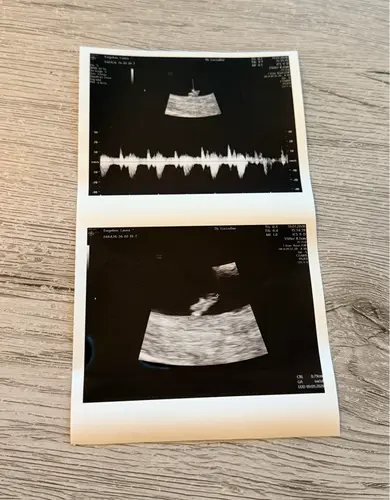

Dit is 8w